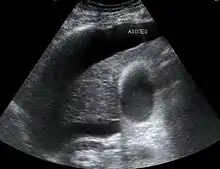

Large volume abdominal ascites

The use of ultrasound has become the standard of care when preparing a patient for paracentesis. Confirmation of an ascitic effusion reduces the risks associated with a dry or blind tap of the abdomen. Anatomic landmarks, such as the midline linea alba approach, were traditionally used as reference points for needle insertion. Phased array or curvilinear ultrasound transducers are typically used in the hospital and outpatient setting to identify ascites in the abdominal cavity. Fluid within the abdominal cavity appears hypoechoic or anechoic (black) on ultrasound. Morison's pouch (hepatorenal recess) is a common starting location in concordance with ultrasound FAST (focused assessment with sonography for trauma) exam. Fluid collection can occur in a number of different locations and may be difficult to find, especially if the patient only exhibits a small volume of ascites. Measurement of the amount of fluid within the abdominal cavity is not necessary or very successful. Identification of sufficient fluid within the abdominal cavity for fluid analysis or to achieve a therapeutic benefit is all that is required to proceed to paracentesis. Ultrasound guidance of the paracentesis can also be used as an additional safety measure to ensure the needle stays within the ascitic fluid and avoidance of important vessels within the abdominal cavity. [5]